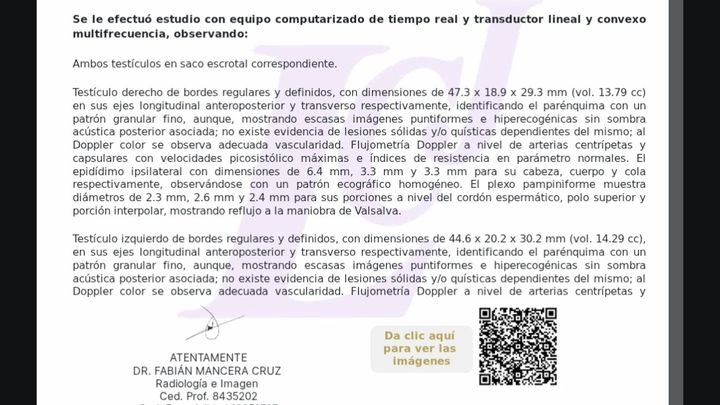

Hola me Llamo Raúl ,tengo 25 años , soy de la CDMX , me atrevo a pedir está ayuda , ya que desde hace unos meses empecé a sentir fuertes dolores en la zona de los testiculos, me hicieron estudios Doppler Testiculares, me detectaron Varicocele de Grado 4 en ambos testículos y microlitiasis testicular en ambos testículos y también tengo hernias en ambos conductos de los testiculos, sufro de fuertes dolores en ambos testículos , eso también está provocando que mi próstata este inflamada, no puedo mantenerme mucho tiempo parado o sentado, me duele mucho al orinar aveces con sangrado, llega el punto en que no puedo ya controlar la orina sale por su cuenta propia, no me atiendo en el IMSS porque el tiempo de espera es mucho , fui a médico particular y me dijeron que ya era urgente la operación porque la sangre no está llegando a los testiculos y se están muriendo, en estos momentos corro riesgo de Esterilidad , y las hernias si no se tratan pueden abrir mas y provocar que los intentos bajen por los conductos de los testiculos y sea una urgencia muy grava y riesgo de una extirpación del intestino si eso llega a pasar , pido su ayuda para poder llegar a esta cantidad, ya que en mi situación es muy difícil poder conseguir todo el dinero.